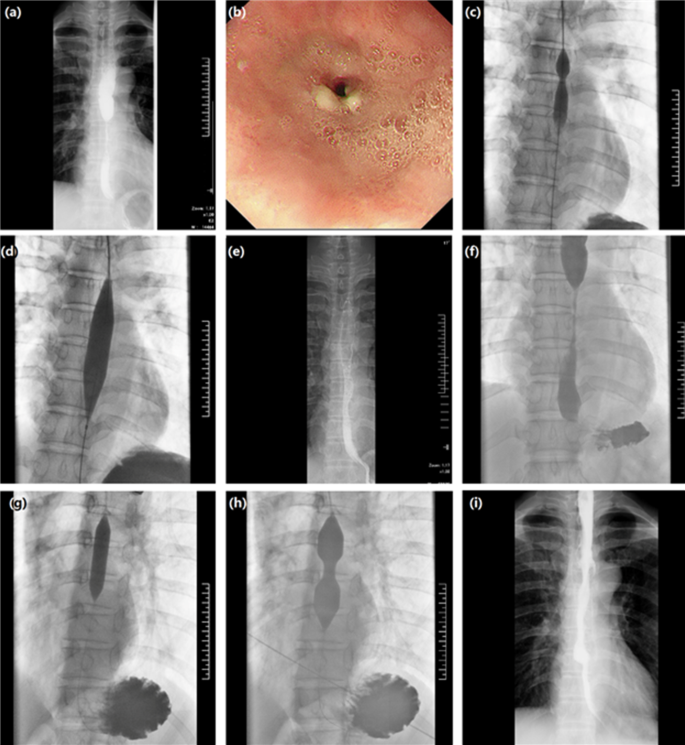

Chest CT and esophagogram or endoscopy was conducted, and all patients were as asked to fast for at least 8 h before the dilatation procedure (Fig. 1). Dilatation procedures were performed under either endoscopic or fluoroscopic guidance. The operators are endoscopists or interventional doctors with at least 10 years of work experience to avoid complications due to their operational inexperience. About 10 ml of iodine contrast was taken orally to show the stricture. A 5 F multipurpose catheter (Cook Corporation, Bloomington, USA) and guidewire were passed through the stricture. Small balloon (< 25 mm in diameter, Bard Peripheral Vascular, Inc; Cook Corporation, Bloomington, USA), large balloon (25–30 mm in diameter, Bard Peripheral Vascular, Inc; Cook Corporation, Bloomington, USA) or DCB (12 mm in diameter, 40, 60–120 mm in length, Beijing Xianreida Medical Technology Co., LTD) was delivered and dilated for 1–3 min (Fig. 2). An immediate esophogram was conducted to show the relief of stricture and the potential complication of rupture.

A male patient underwent large balloon dilatation for anastomotic stricture. (a) An esophagogram showed severe stricture at the level of the sternoclevicular joint 2.8 months after esophagectomy for esophageal cancer. (b) Dilatation using Bard large balloon (26 mm in diameter, 40 mm in length) was done by positioning the balloon within the stricture. (c) The balloon catheter was dilated and inflated with 50% diluted contrast medium. (d) The esophagography showed a relief of esophageal stricture 10.1 months after dilatation, and the patient is able to eat normal diet during follow-up.